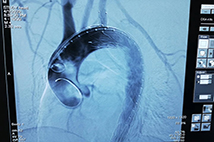

不用“开膛剖肚”,人体的“不定时炸弹”——主动脉夹层动脉瘤就被解除了。近日(4月1日),无锡明慈医院心脏中心成功为一名40岁的“主动脉夹层动脉瘤”患者实施了“夹